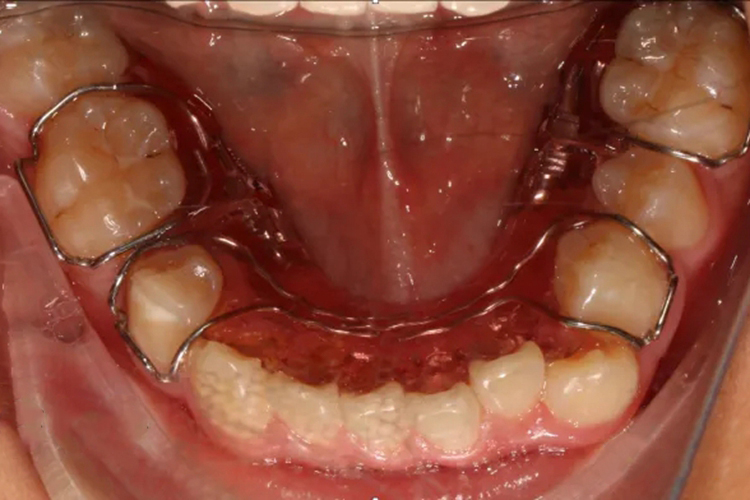

下颌扩弓正畸常采用四眼簧扩弓器,主要根据下牙弓的大小,应用镍铬合金片制作合适的牙带环,并沿着第一磨牙和前磨牙带环舌侧双圆管形成的轨道走形,形成桥梁。由于下颌内有舌头,四眼簧扩弓器可以避开舌头活动区域,在不影响、限制舌头活动的情况下进行治疗,以减少患者痛苦。